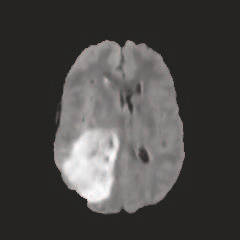

Multi-modal medical image completion has been extensively applied to alleviate the missing modality issue in a wealth of multi-modal diagnostic tasks. However, for most existing synthesis methods, their inferences of missing modalities can collapse into a deterministic mapping from the available ones, ignoring the uncertainties inherent in the cross-modal relationships. Here, we propose the Unified Multi-Modal Conditional Score-based Generative Model (UMM-CSGM) to take advantage of Score-based Generative Model (SGM) in modeling and stochastically sampling a target probability distribution, and further extend SGM to cross-modal conditional synthesis for various missing-modality configurations in a unified framework. Specifically, UMM-CSGM employs a novel multi-in multi-out Conditional Score Network (mm-CSN) to learn a comprehensive set of cross-modal conditional distributions via conditional diffusion and reverse generation in the complete modality space. In this way, the generation process can be accurately conditioned by all available information, and can fit all possible configurations of missing modalities in a single network. Experiments on BraTS19 dataset show that the UMM-CSGM can more reliably synthesize the heterogeneous enhancement and irregular area in tumor-induced lesions for any missing modalities.